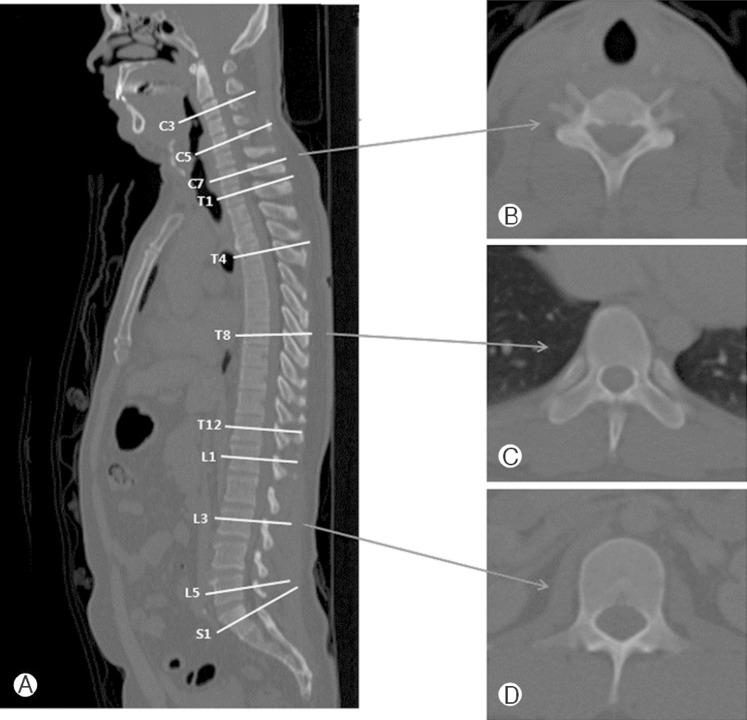

From PET/CT, axial bone-window CT of 83 young adults (20-29 years) were obtained, and we measured AP diameters of C3, C5, C7, T1, T4, T8, T12, L1, L3, L5 and S1. We also measured exposed AP diameter of C3, C5, C7, T1 and T2 above imaginary line for laminectomy.

The shortest mean AP diameter was at C5 (14.5±1.5 mm), and the longest was at S1 (17.4±2.3 mm). AP diameter increased from C3 (14.6±1.1 mm) to T1 (16.1±1.2 mm) at cervical spine. In the thoracic spine, the diameter gradually decreased from T1 (16.1±1.2 mm) to T8 (14.6±1.3 mm) and increased to T12 (16.7±1.2 mm). The diameter decreased from L1 (16.7±1.3 mm) to L3 (15.7±1.9 mm), and it increased to S1 (17.4±2.3 mm) at lumbar spine. Exposed AP diameter above imaginary line for laminectomy was the longest at C3 (4.8±1.2 mm) and gradually decreased to T1 (3.3±0.9 mm) and T2 (0 mm).

Spinal AP diameter was the shortest in the mid-cervical area (C5) and increased to the upper thoracic area. From the upper thoracic vertebra, the diameter gradually decreased to the mid-thoracic vertebra (T8) and then increased to the lower thoracic vertebra. Lumbar vertebra also was similar with thoracic vertebra. Below T2, there was no exposed dural sac after laminectomy. This means that restenosis by post-laminectomy membrane formation can occur above T1.

从PET/CT获取83名20 - 29岁年轻成年人的轴向骨窗CT图像,测量C3、C5、C7、T1、T4、T8、T12、L1、L3、L5和S1的前后径。我们还测量了椎板切除假想线上方C3、C5、C7、T1和T2的暴露前后径。

平均前后径最短处为C5(14.5±1.5mm),最长处为S1(17.4±2.3mm)。颈椎处前后径从C3(14.6±1.1mm)至T1(16.1±1.2mm)增大。胸椎处,直径从T1(16.1±1.2mm)逐渐减小至T8(14.6±1.3mm),然后增大至T12(16.7±1.2mm)。腰椎处直径从L1(16.7±1.